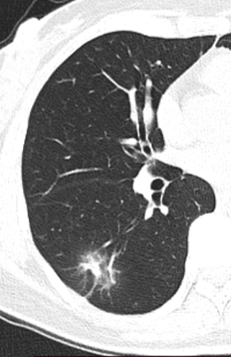

肺癌是发病率和死亡率增长最快 对人群健康和生命威胁最大的恶性肿瘤之一 换言之 发现得越早 治疗效果越好 我们与新华日报交汇点直播平台 江苏省科学传播中心合作 并邀请到了江苏省人民医院(南京医科大学第一附属医院)胸外科主任医师朱全 和我们聊一聊从肺结节到肺癌,如何实现精准诊疗? 专家简介 朱全,主任医师,江苏省人民医院胸外科副主任。中华医学会胸心血管外科学分会胸腔镜学组委员,中华医学会江苏省胸外科分会委员。 01 肺结节的性质 肺结节:< 3厘米 主要是指肺实质内单发或多发直径不超过 3 厘米 的圆形或类圆形结节影。不伴肺不张、肺钙化、肺门淋巴结肿大或胸膜渗出。 结节: <8毫米时称作亚厘米结节 <4毫米称作微结节 肿块: ≥ 3厘米 02 肺结节的分类 (1)实性结节 (2)半实性结节 (纯磨玻璃结节、混合磨玻璃结节) 实性结节 混合磨玻璃结节 结节分类 磨玻璃样结节 03 肺结节≠肺癌 •实性结节恶性率仅7% •部分实性结节恶性率为63% •纯磨玻璃结节恶性率为18% •>20 毫米的结节恶性率有80% 肺磨玻璃肺结节的演变 01胸部X光平片 对肺癌的漏诊率30% 不能发现肺小结节 02 薄层CT 5mm层厚已成为历史---导致误诊! 薄层CT比常规CT提供了7-10倍信息 (普通CT 60张对比 薄层CT 360-600张) 03 正确使用PET/CT • 能够评估结节的代谢活性。 • 对大于1厘米的实性结节有意义 • 对纯磨玻璃和混合性磨玻璃结节无效 • 不易区分炎症和结核 强调!!! 磨玻璃结节要经过随访 2-3个月的随访很重要 炎症的比例10% 随着时间会消失 肺结节CT影像AI辅助检测 外科手术的微创化 切口的微创化 全胸腔镜→3孔→2孔→单孔 肺切除范围的变化 非解剖性肺切除:楔形 解剖性肺切除:全肺切除、肺叶切除、肺段切除术、肺亚段切除术、肺次亚段切除术 肺段切除 早期肺癌的微创治疗外科手术的精准化 早期肺癌外科治疗中的规则: 保证肿瘤学效果是首要任务保留更多有功能的肺组织 三维CT支气管血管成像(3D-CTBA)肺结节与早期肺癌